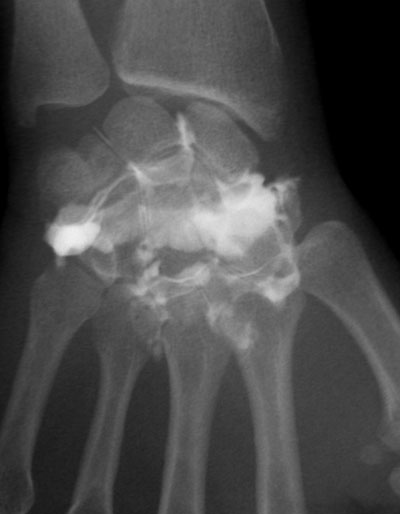

Poignet

Rupture du ligament triangulaire (flèche de droite)

Rupture des ligaments ulno-carpien et luno-pyramydal, chondropathie dégénérative (flèche du bas)